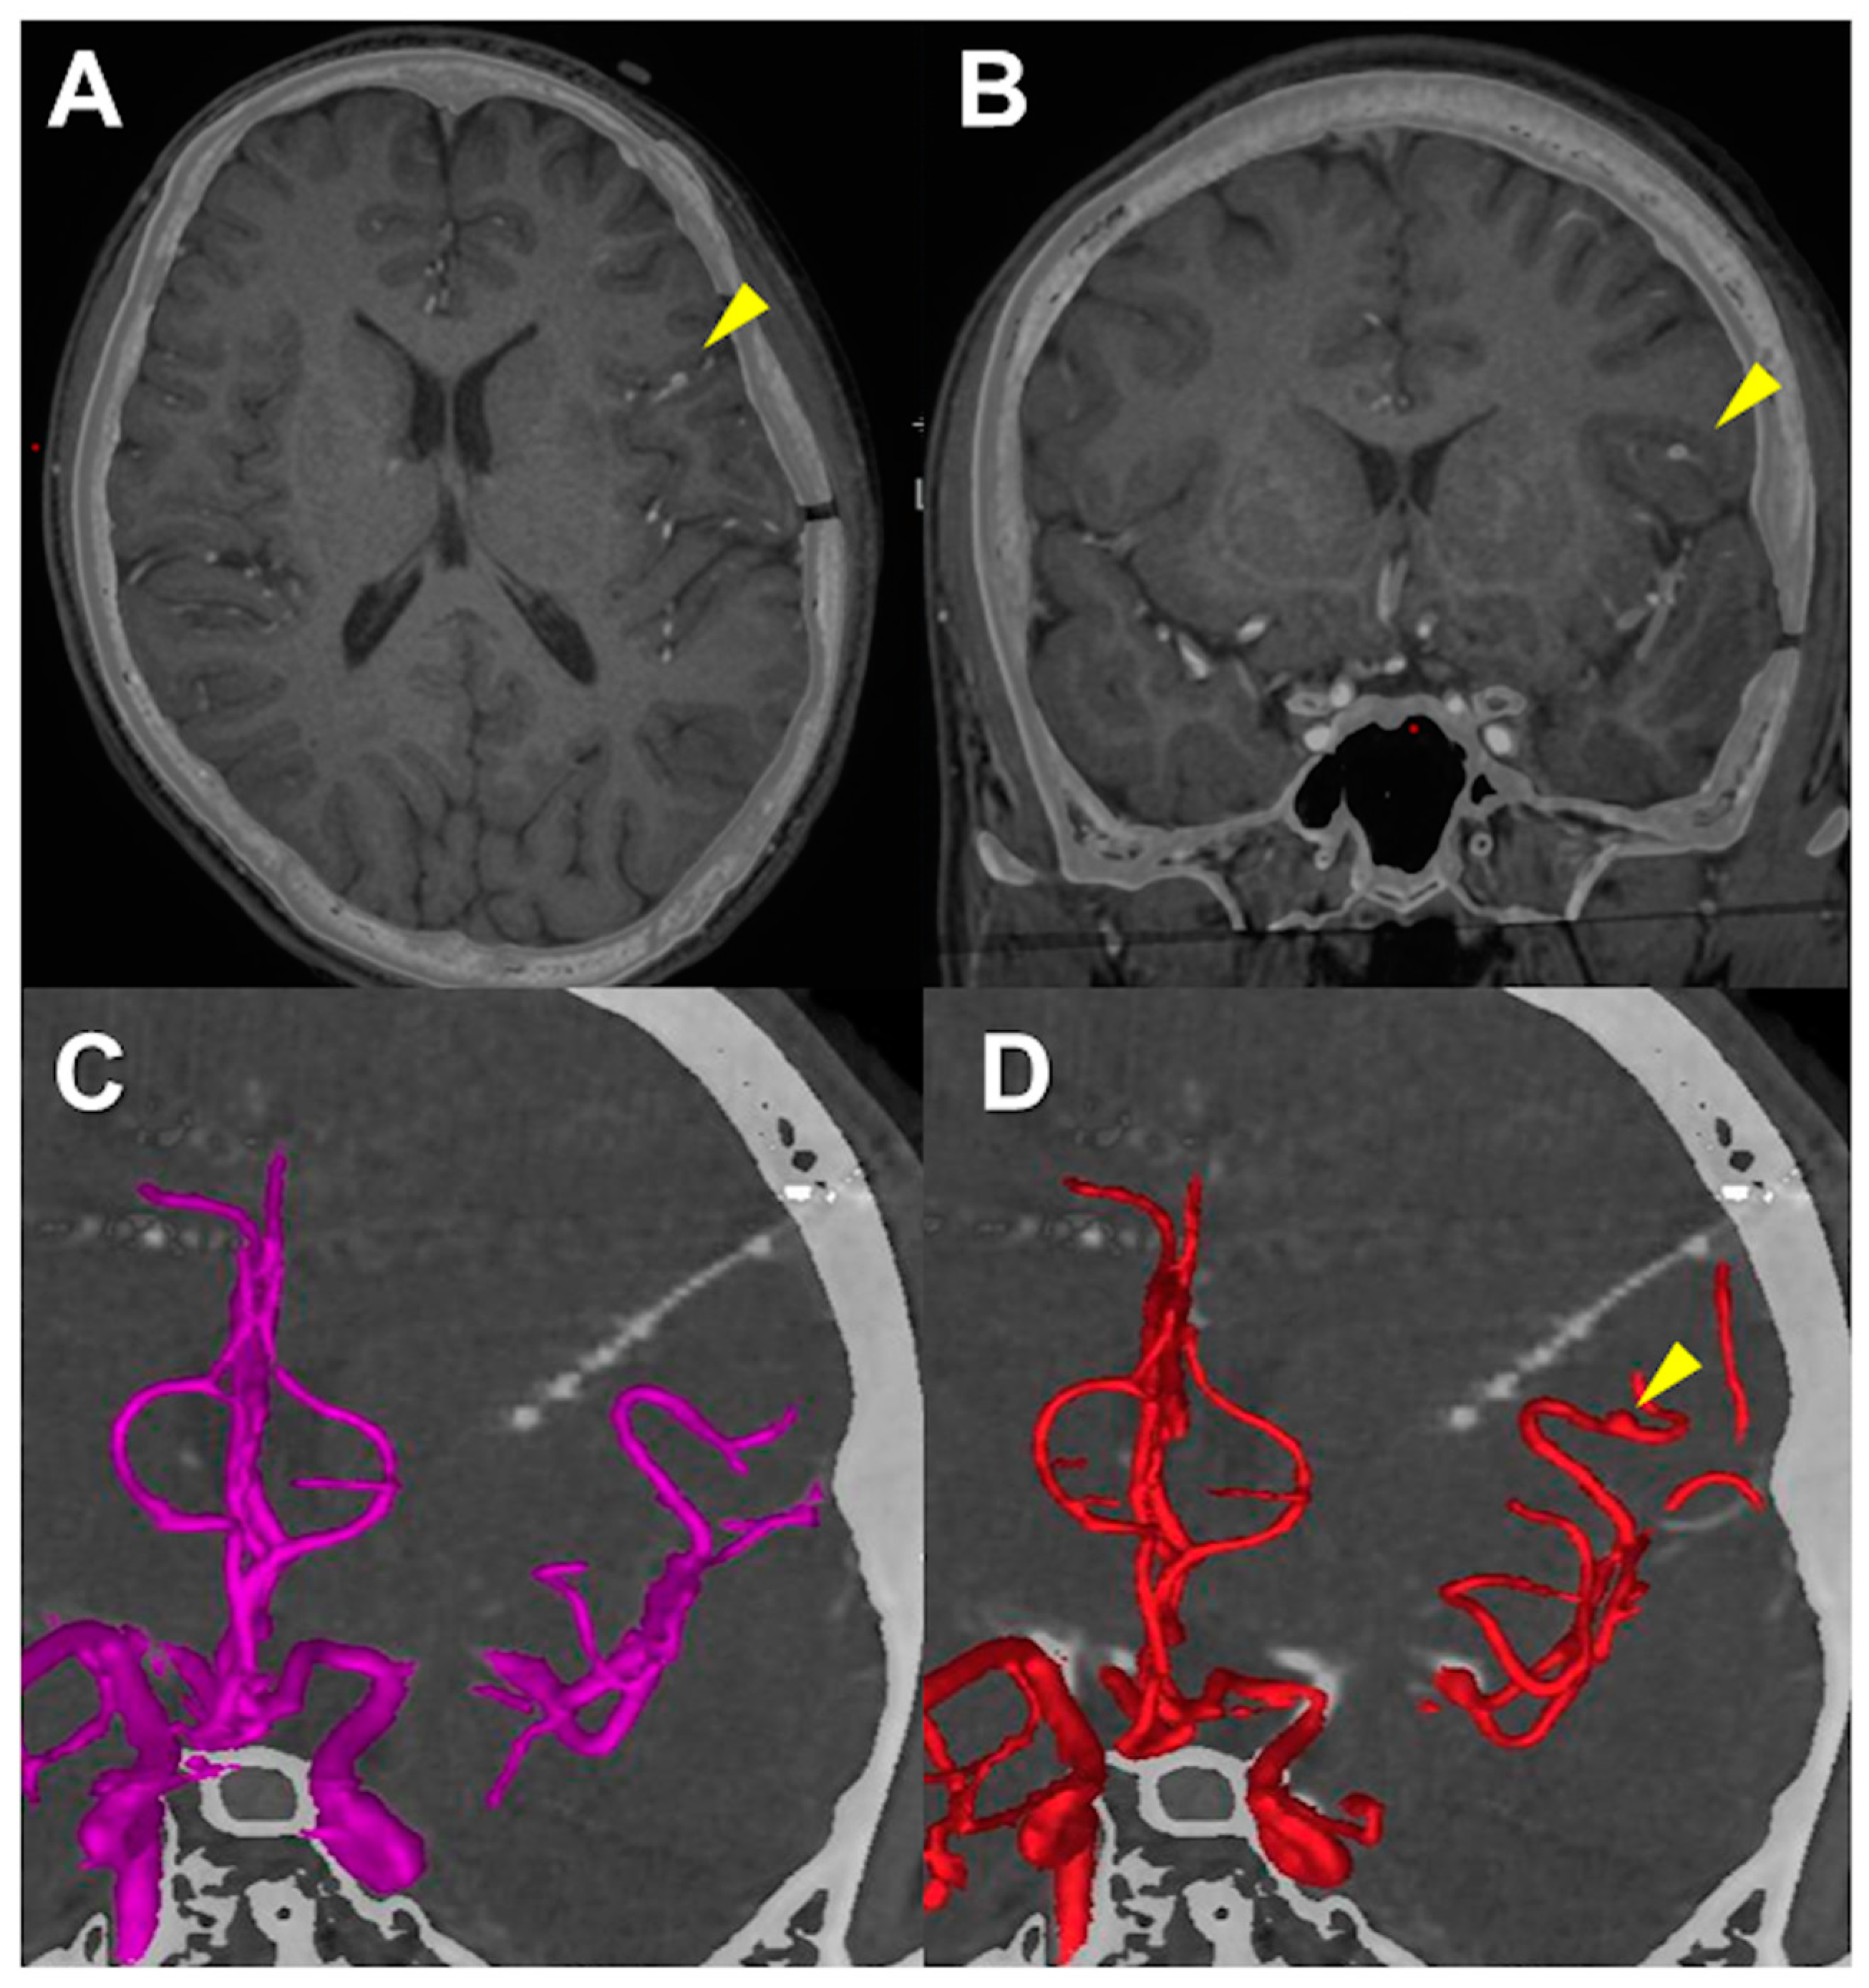

| Electrode # | Side | Entry | Target |

|---|---|---|---|

| 1 | Left | SFG | anterior Orb |

| 2 | Left | IFG | posterior Orb |

| 3 | Left | MFG | anterior Cing |

| 4 | Left | IFG | anterior Cing |

| 5 | Left | FEF | middle Cing |

| 6 | Left | IFG | middle Cing |

| 7 | Left | anterior SFG | SMA |

| 8 | Left | posterior SFG | SMA |

| 9 | Left | PreCG | insula |

| 10 | Right | SFG | SMA |

| 11 | Right | MFG | middle Cing |